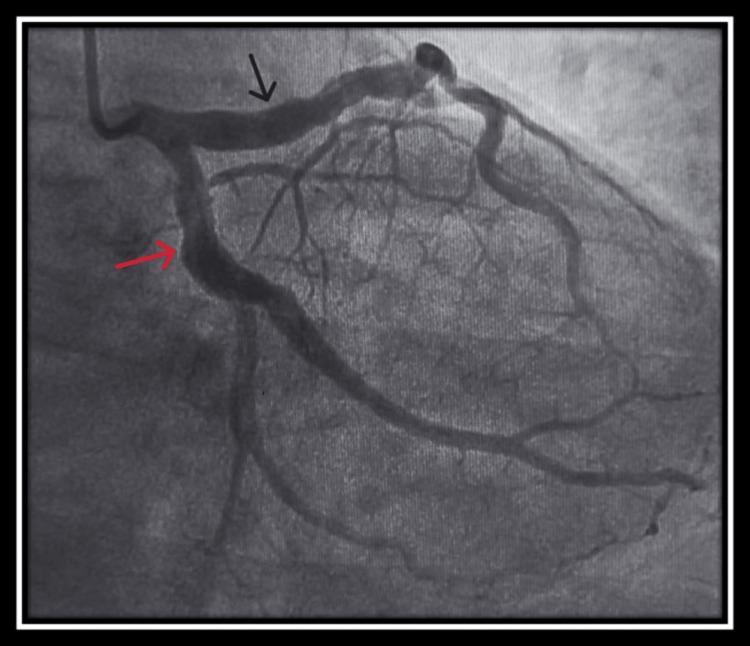

Coronary artery ectasia (CAE) is a rare condition, affecting 3%-8% of patients with atherosclerotic coronary artery disease, and is characterized by the abnormal dilatation of the coronary arteries. While the etiology of coronary artery ectasia encompasses a myriad of acquired and genetic factors, its pathogenesis still remains a subject of investigation. The clinical manifestations are varied, ranging from asymptomatic cases to chest angina and myocardial infarction. Coronary angiography remains the gold standard for diagnosing CAE. We herein report four cases of coronary ectasia: the first involving myocardial infarction, the second associated with bicuspid aortic valve with severe aortic regurgitation, the third detected during coronary angiography for moderate left ventricular dysfunction, and the last one detected during coronary angiography for stable angina. The aims of our study are to highlight the diversity of clinical presentations as well as the challenge of management, given that there are no universal treatments or guidelines.

冠状动脉扩张(CAE)是一种罕见病症,在动脉粥样硬化性冠状动脉疾病患者中占3%-8%,其特征为冠状动脉异常扩张。虽然冠状动脉扩张的病因包括众多后天因素和遗传因素,但其发病机制仍是一个研究课题。临床表现多样,从无症状病例到心绞痛和心肌梗死不等。冠状动脉造影仍然是诊断CAE的金标准。我们在此报告4例冠状动脉扩张病例:第一例伴有心肌梗死,第二例与二叶式主动脉瓣伴严重主动脉瓣反流相关,第三例在冠状动脉造影时因中度左心室功能障碍被检测出,最后一例在冠状动脉造影时因稳定型心绞痛被检测出。鉴于目前尚无通用的治疗方法或指南,我们研究的目的是强调临床表现的多样性以及管理方面的挑战。